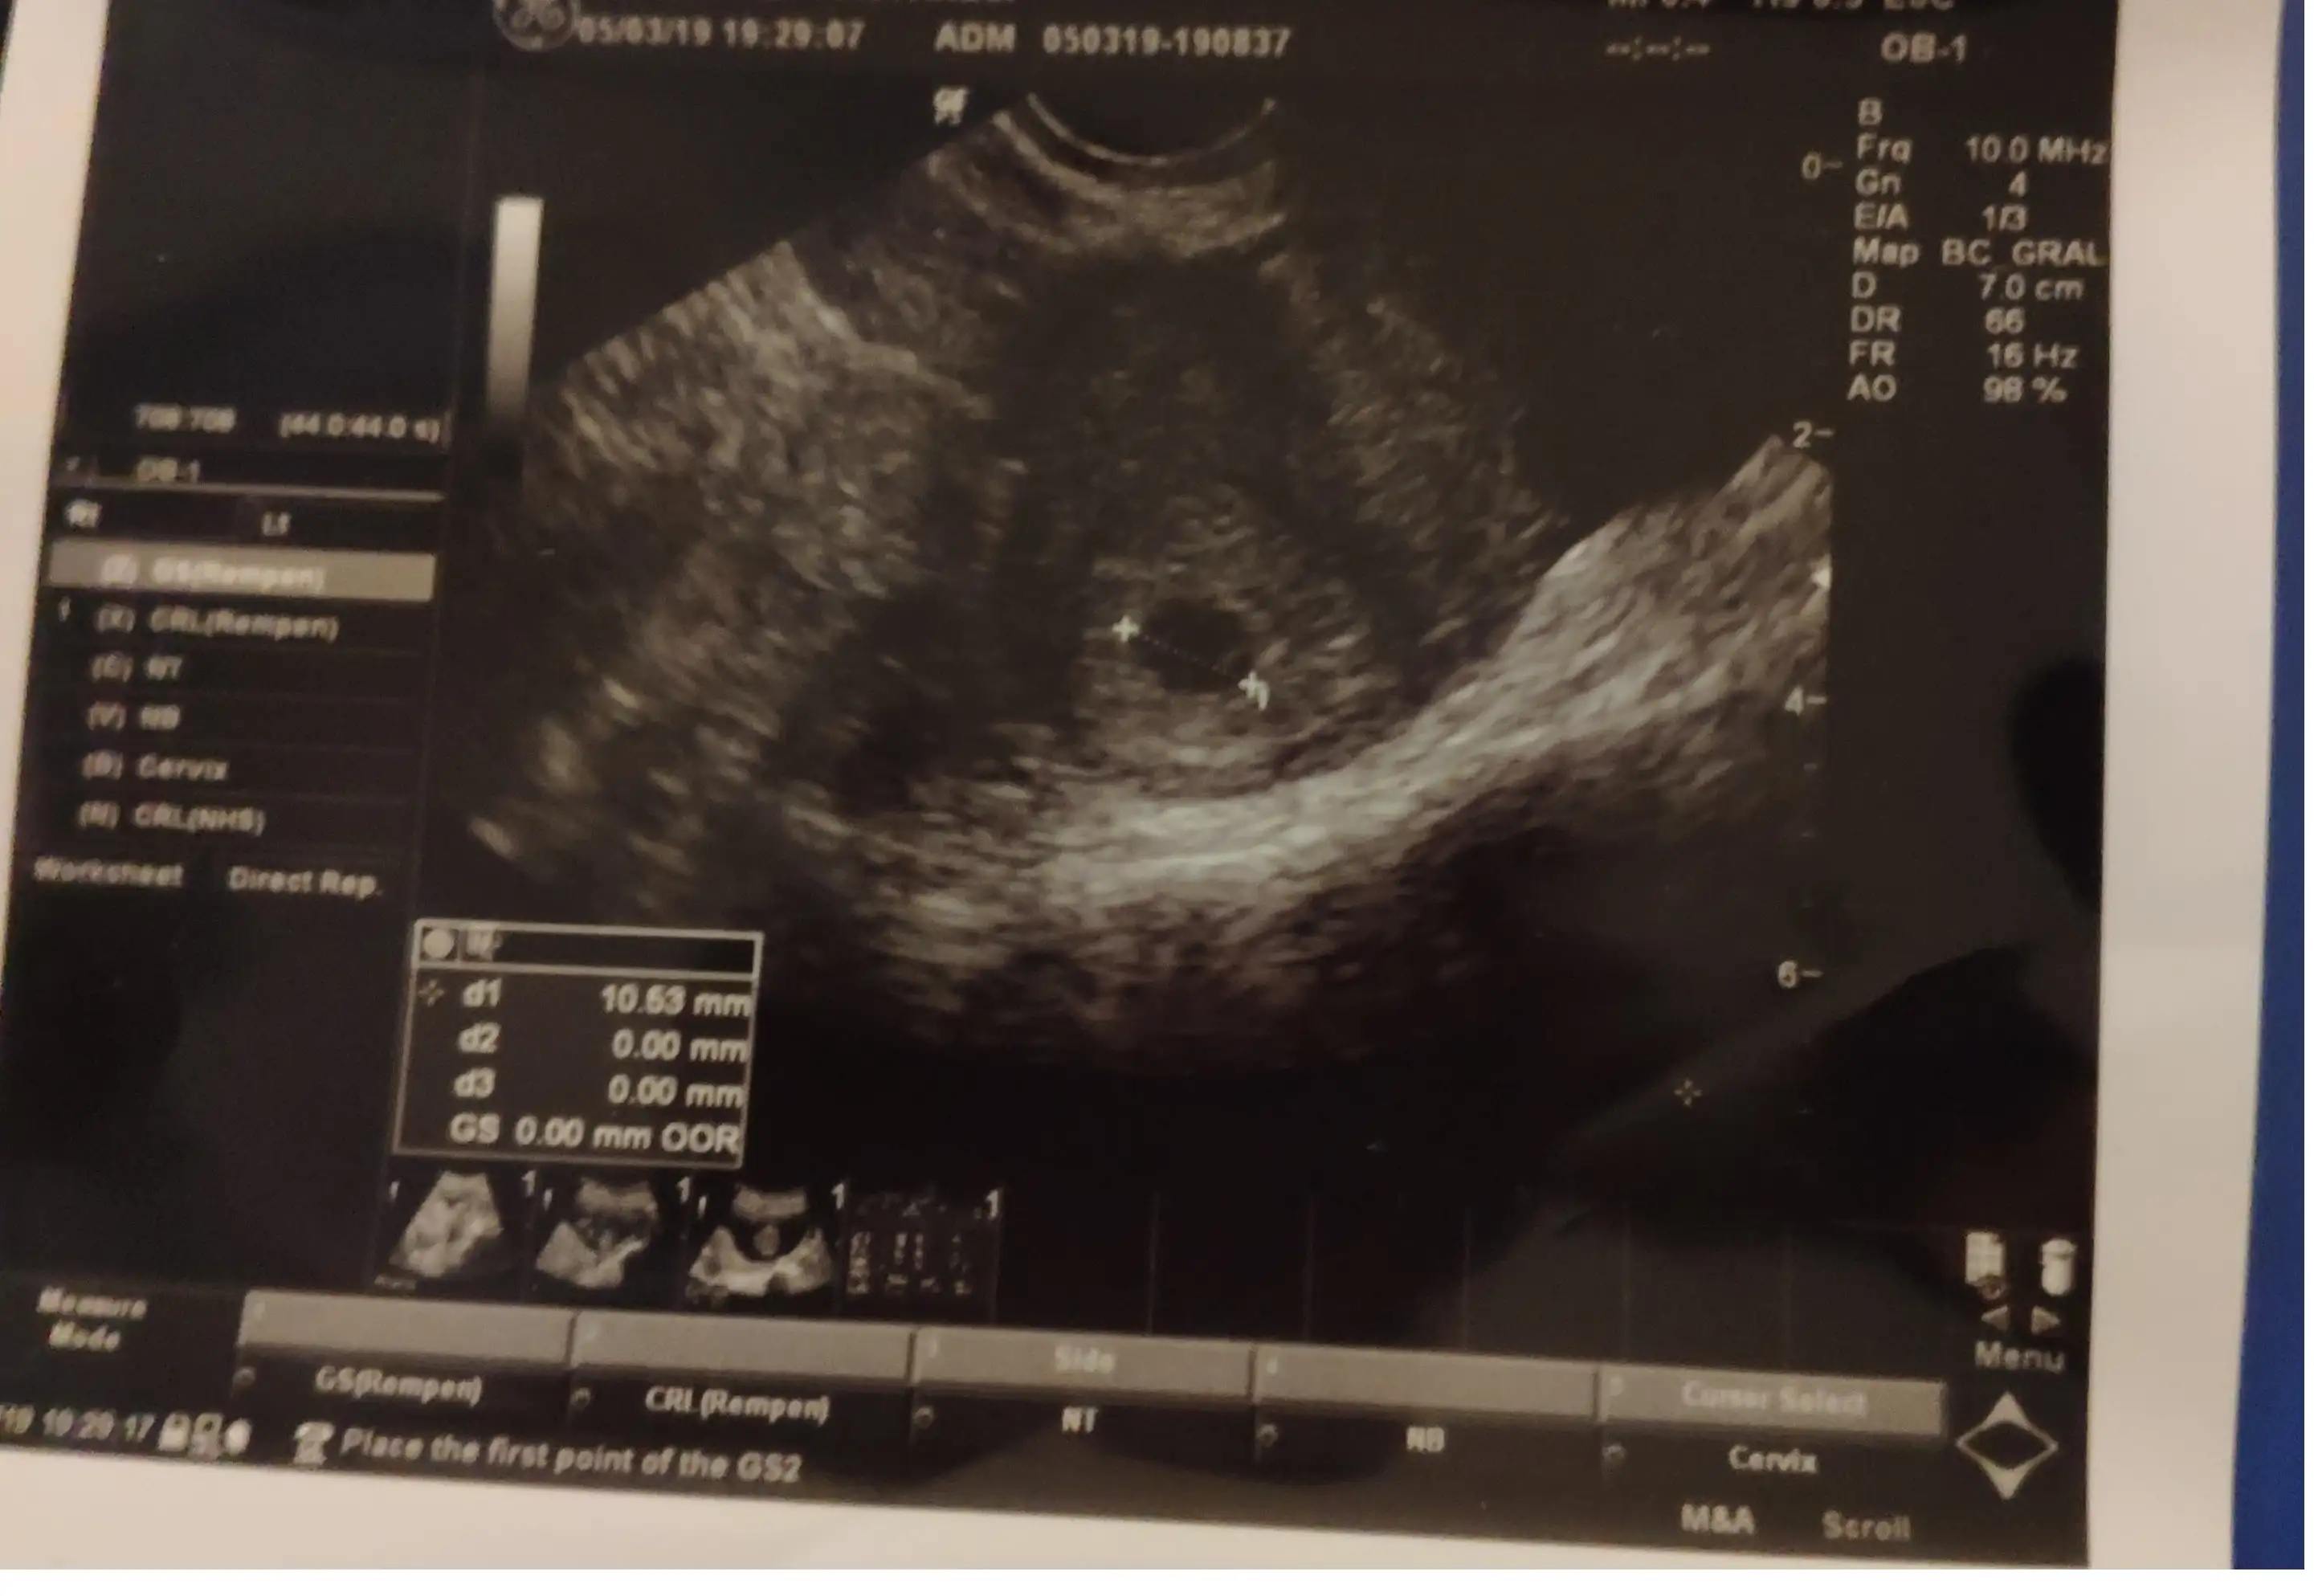

Erkek gibi hissettim canım hayırlısı olsunMerhaba, ilk ultrason alttan 5 haftalık , ikinci ultasonda karından 6+2 sizce cinsiyeti nedir ?

Sola tMerhaba, ilk ultrason 5 haftalık , ikinci ultasonda 6+2 sizce cinsiyeti nedir ?Eki Görüntüle 2245201 Eki Görüntüle 2245202

erkek gibi CanımMerhaba, ilk ultrason alttan 5 haftalık , ikinci ultasonda karından 6+2 sizce cinsiyeti nedir ?